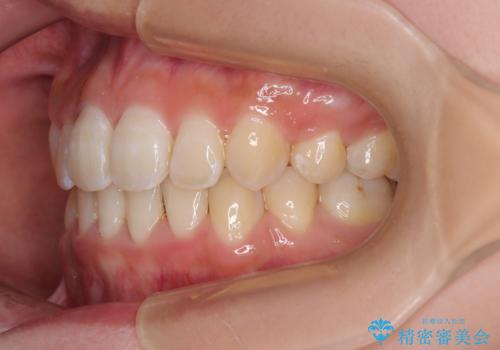

- 前歯のデコボコと唇の閉じにくさを気にして来院された患者様です。

単純に上下左右の第一小臼歯4本を抜歯して口元の突出感を改善することも考えられましたが、上顎骨よりも下顎骨の幅が広いため、より良い咬み合わせを達成することを目的として、急速拡大装置を用いて上顎骨を拡大することとしました。